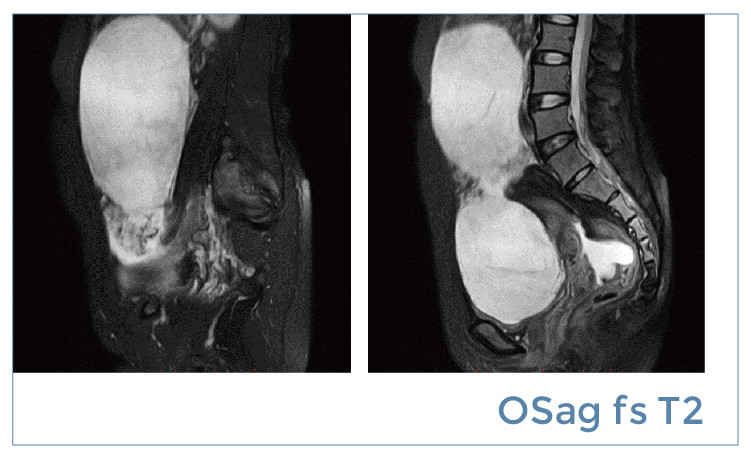

【朗润影像档案】磁共振影像病例分享(编号20190419)